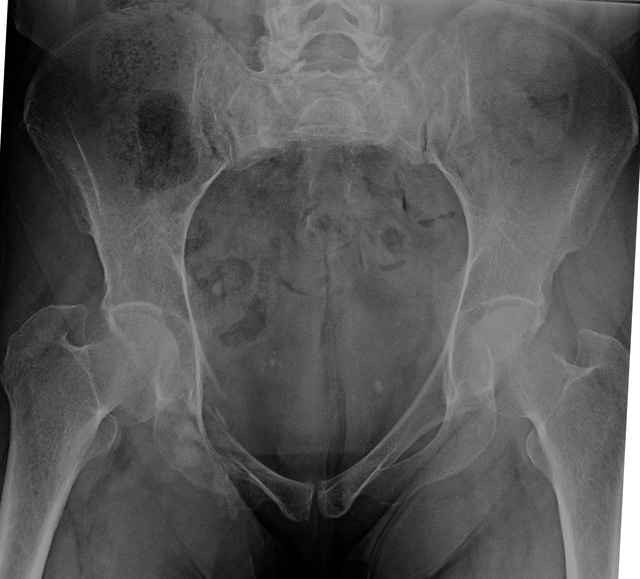

Percutaneous Fixation

(B) Ramus-Retrograde

2 TransIliac-TransSacral

Upper Segment